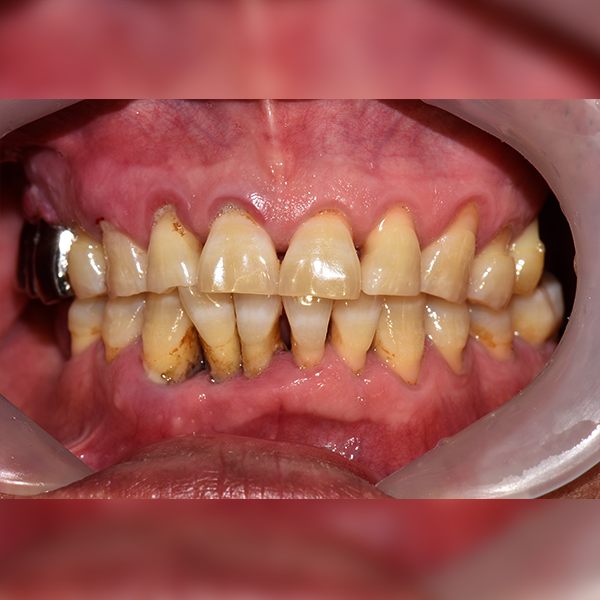

3. Тохиолдол.223 50-аад насны И*ган 2019-01-11 / 2019-07-24

Тохиолдол.223 50-аад насны И*ган 2019-01-11 / 2019-07-24

Before Before

After After